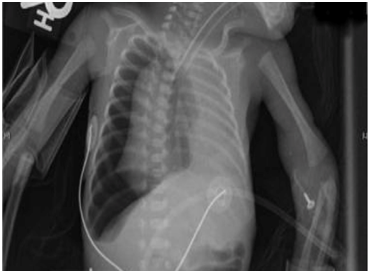

- AP Chest radiograph:

- Air in the pleural space.

- Flattening of the diaphragm on the affected side.

- Shift of the mediastinum away from the pnuemothorax (Figure 1).

Figure 1 Neonate with Right Tension Pneumothorax.